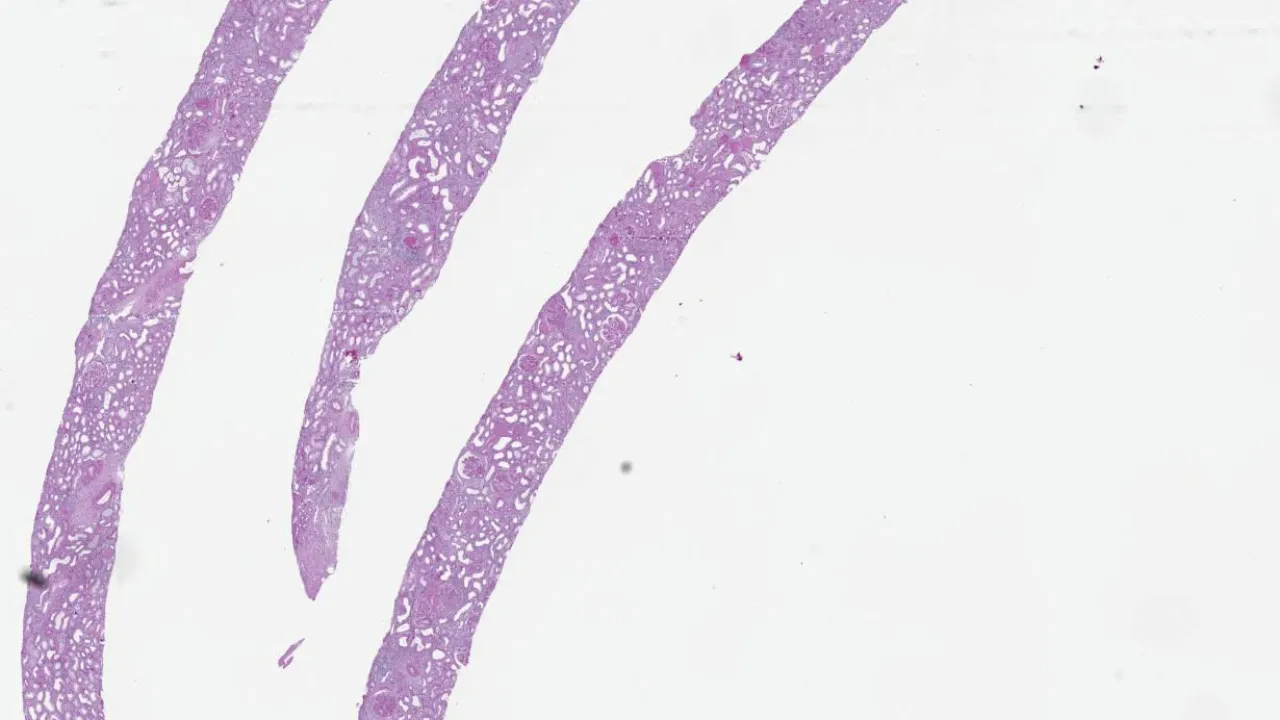

Kidney, Loop of Henle